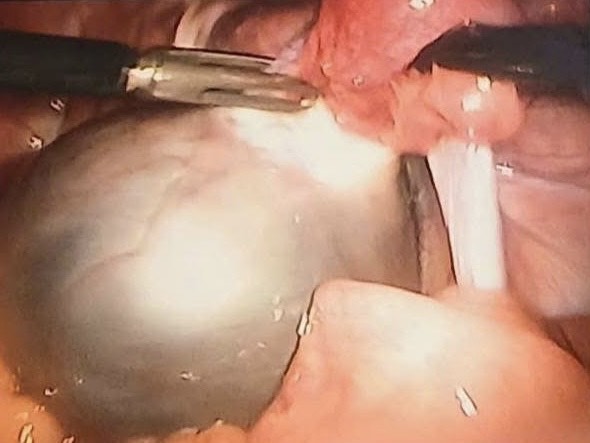

Vừa qua, khoa Phụ sản - Bệnh viện đa khoa (BVĐK) Chương Mỹ đã tiếp nhận một trường hợp bệnh nhân nữ 19 tuổi đến khám vì đau tức bụng dưới. Qua thăm khám và siêu âm, phát hiện có khối u buồng trứng kích thước 70x58mm. Sau khi hội chẩn, các bác sĩ quyết định phẫu thuật nội soi cắt u buồng trứng.

Phẫu thuật nội soi cắt u buồng trứng bảo tồn tối đa chức năng sinh sản cho người bệnh.

Đây là một phương pháp phẫu thuật hiện đại đòi hỏi chuyên môn sâu, sự khéo léo và tinh tế của phẫu thuật viên. Giúp bệnh nhân trẻ tuổi điều trị khối u buồng trứng nhưng vẫn bảo tồn tối đa chức năng sinh sản, nội tiết cho người bệnh. Ưu điểm của phẫu thuật nội soi là giúp phóng đại hình ảnh, hỗ trợ thao tác tinh tế và chính xác hơn từ đó bóc tách và để lại phần buồng trứng lành, hạn chế chảy máu, giảm nguy cơ dính, đường mổ nhỏ đảm bảo thẩm mỹ và giúp người bệnh mau chóng phục hồi sức khoẻ sau mổ.

Ca phẫu thuật đã diễn ra thuận lợi và an toàn, với phẫu thuật viên chính là BSCKII Nguyễn Tiến Thành - Trưởng khoa Phụ sản, BVĐK Chương Mỹ. Bệnh nhân sau mổ 2 ngày đã ăn uống trở lại và hướng dẫn tập vận động đi lại bình thường, tình trạng vết mổ liền tốt và đau ít tại vết mổ.

BSCKII Nguyễn Tiến Thành - Trưởng khoa Phụ sản chia sẻ: "Điều quan trọng trong điều trị u buồng trứng ở phụ nữ trẻ là phải điều trị triệt để nhưng đồng thời bảo tồn tối đa phần buồng trứng lành để đảm bảo khả năng sinh sản và nội tiết cho người bệnh. Phẫu thuật nội soi là lựa chọn tối ưu giúp giảm sang chấn, ít để lại sẹo, hồi phục nhanh và vẫn giữ được phần buồng trứng lành."